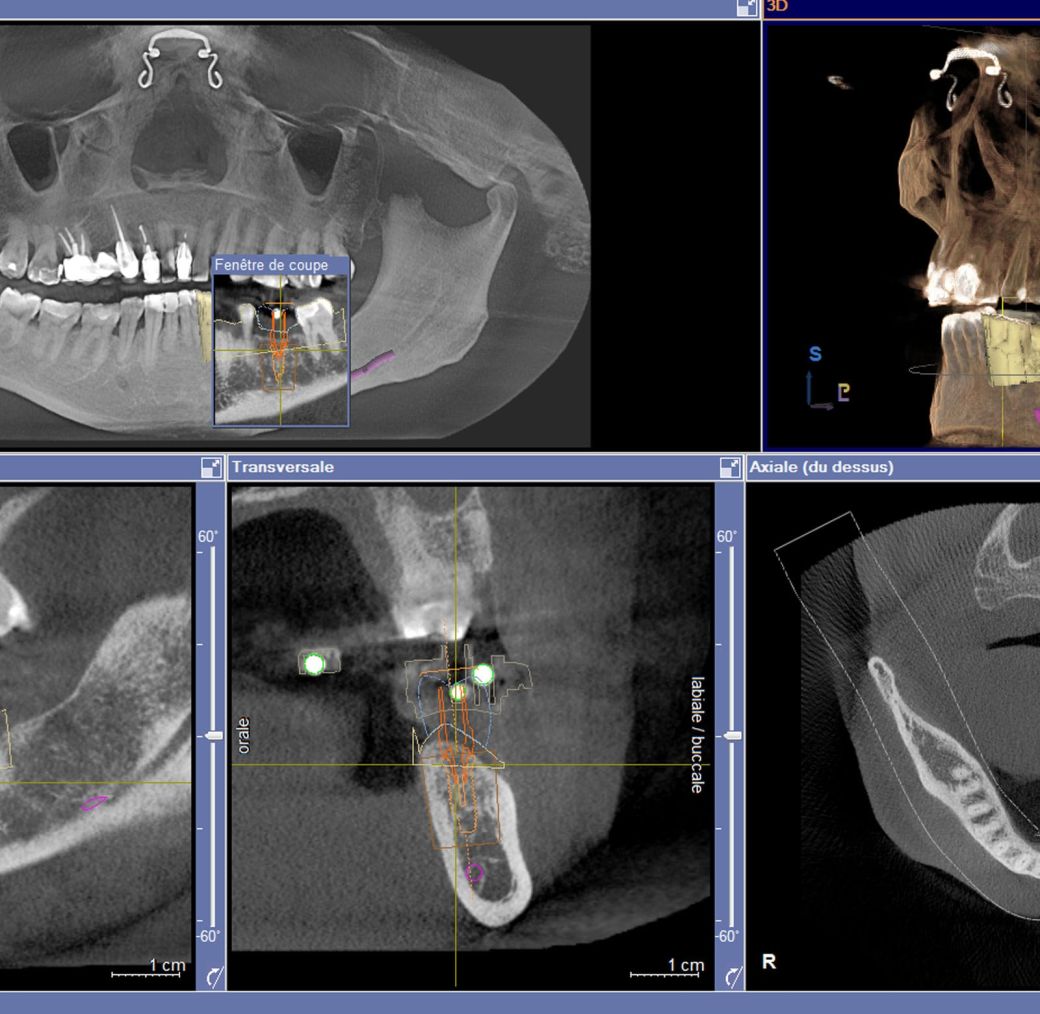

Le Cône Beam (CBCT)

C’est l’examen de choix pour la réalisation de la planification implantaire.

La planification implantaire

La planification implantaire consiste à déterminer le choix du nombre, de la longueur, du diamètre et de la position des implants, ainsi que leur orientation dans les différents plans de l’espace.

Grace au système CEREC, le projet prothétique supra-implantaire peut déjà être pris en compte. Cette planification axée sur la prothèse assure un positionnement optimal de l’implant avec le guide chirurgical CEREC GUIDE.

Dans ce cas clinique, la planification implantaire tient compte, pour la pose d’un implant localisé sur le site 36, du projet prothétique final (ici une couronne matérialisée en bleu).

Le nerf dentaire inférieur, élément noble à respecter dans cette chirurgie implantaire, est ici schématisé en violet.